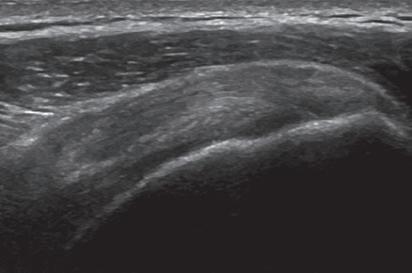

SONOGRAPHIC APPEARANCES OF NORMAL STRUCTURES

Musculoskeletal structures have characteristic appearances on ultrasound imaging.2 Normal tendons appear hyperechoic with a fiber-like or fibrillar echotexture (see Fig. 1.4).3 At close inspection, the linear fibrillar echoes within a tendon represent the endotendineum septa, which contain connective tissue, elastic fibers, nerve endings, blood, and lymph vessels.3 Continuous tendon fibers are best appreciated when they are imaged long axis to the tendon. On such a long axis image, by convention the proximal aspect is on the left side of the image, with the distal aspect on the right. In short axis, normal hyperechoic tendon fibers appear as bristles of a brush seen on end (see Fig. 1.9A). Normal muscle tissue appears relatively hypoechoic (Fig. 1.6). At closer inspection, the hypoechoic muscle tissue is separated by fine hyperechoic fibroadipose septa or perimysium, which surrounds the hypoechoic muscle bundles. The surface of bone or calcification is typically very hyperechoic, with posterior acoustic shadowing and possibly posterior reverberation if the surface of the bone is smooth and flat (Fig. 1.6). The hyaline cartilage covering the articular surface of bone is hypoechoic and uniform (Fig. 1.7A and B), whereas the fibrocartilage, such as the

FIGURE 1.4 Normal Patellar Tendon. Ultrasound image of patellar tendon in long axis (arrowheads) shows hyperechoic fibrillar echotexture. P, Patella; T, tibia.